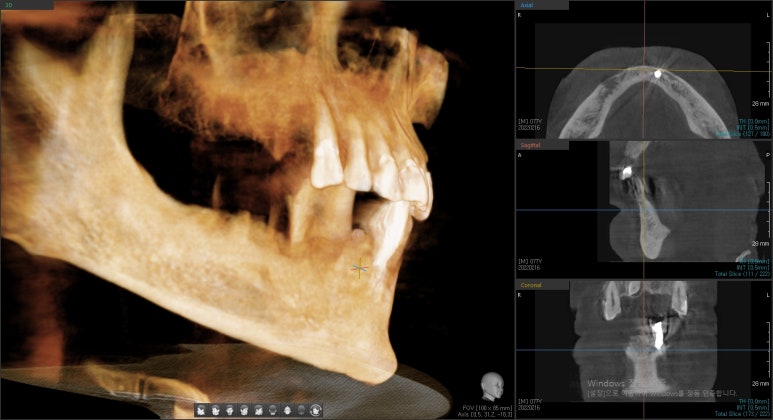

연세예감치과의 3차원 CT 사진

임플란트 심기는 곳에 임플란트 뿌리 주변으로 위아래 양옆 모두 3차원적으로 뼈가 다 둘러 있는 것이 중요한데요,

따라서 치과의사선생님의 소견에 따라 CT등을 찍어본 후

임플란트가 들어갈 곳의 뼈의 상태를 확인하여

발치 후 즉시임플란트가 가능한지, 아니면 3개월이나 몇개월 기다렸다가 임플란트가 가능한지 결정된다고 하겠습니다.

따라서 위 할아버지와 같이 같은 분이라도 뺄 치아=곧 임플란트가 들어갈 곳의 바로 근접한 주변 뼈 상태에 따라

발치즉시 임플란트가 가능할지, 발치 후 뼈가 회복되기를 기다렸다가 임플란트 수술을 해야할지

결정이 됩니다.